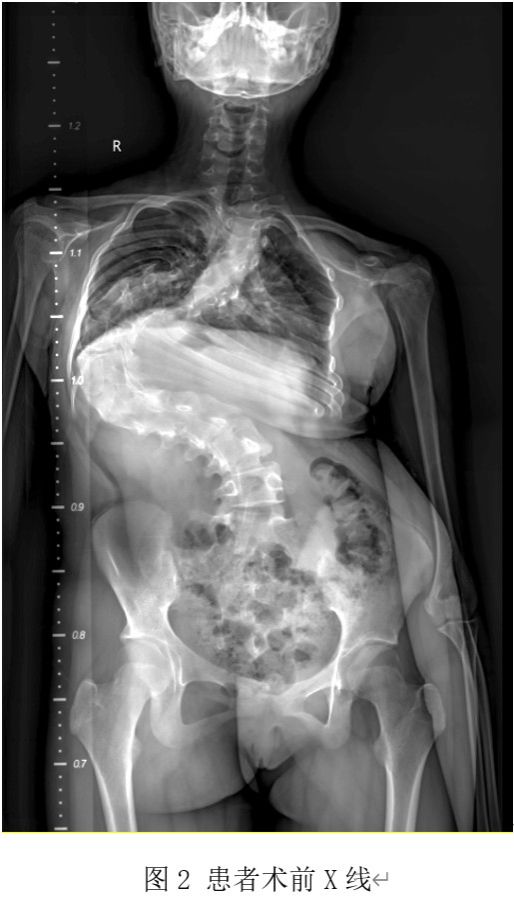

此次接受手术的患者为一名13岁青少年,十余年前无意间发现脊柱向侧后方弯曲,且呈进行性加重趋势。近年来,患者背部逐渐出现明显的侧弯后凸畸形,胸廓畸形严重,心肺功能受到极大影响,日常生活受到严重困扰。患者家属曾辗转全国多家知名医院求医,但均因手术难度及风险极大而放弃治疗。最终,患者慕名来到西安交通大学第二附属医院骨科中心脊柱与骨肿瘤病区,寻求希望。

入院后经详细检查,患者脊柱畸形极为严重,侧弯Cobb角超过120度,部分椎体旋转几乎呈水平状态,椎旁肌肉僵硬,胸廓畸形明显,且肺功能下降。如此极重度的脊柱侧弯不仅影响患者的外观,更对心肺功能等造成严重威胁,手术矫形难度极大,风险极高。面对如此复杂的病情,西安交通大学第二附属医院骨科中心脊柱与骨肿瘤病区高度重视,迅速组织了多学科专家团队进行会诊。团队包括脊柱外科专家、麻醉科专家、影像科专家以及护理团队等,共同为患者制定个性化的手术方案。

在脊柱与骨肿瘤病区王栋主任的指导下,手术团队采用渐进式治疗方案,首先进行头颅及双下肢骨牵引术,通过上下两个方向同时逐渐牵拉,将弯曲僵硬的脊体牵长、拉软,为手术做好准备。持续牵引2周后,患者的胸廓畸形、椎旁肌肉僵硬等情况得到较大改善,身高也有所增加。术前应用3D打印技术模拟手术方案,术中全程神经监护,充分备血,确保手术的精准性和安全性。

在麻醉医师李喆和手术室护士王娟平、杨于瑶的熟练配合下,经过近10小时的紧张手术,团队成功完成了脊柱的全段矫形。手术过程顺利,无神经损伤等相关并发症发生。手术从上午10时持续到晚8时,体现了手术的高难度和复杂性。术中出血量较大,但通过及时的输血和补充血容量等措施,确保了患者的生命安全。术后手术矫形率达到60%以上,患者的脊柱序列得到显著改善。术后患者即可平卧,背部畸形显著改善,身高增加了7cm以上,双下肢活动感觉运动良好。经过积极的康复治疗,患者逐渐恢复正常的生活和学习。